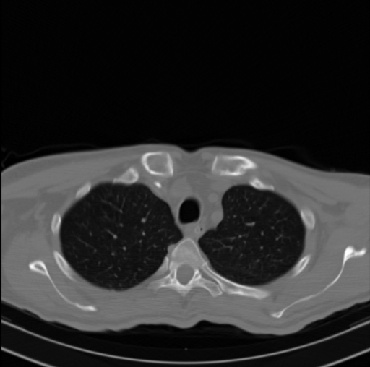

Early and reliable COVID-19 diagnosis based on chest 3-D CT scans can assist medical specialists in vital circumstances. Deep learning methodologies constitute a main approach for chest CT scan analysis and disease prediction. However, large annotated databases are necessary for developing deep learning models that are able to provide COVID-19 diagnosis across various medical environments in different countries. Due to privacy issues, publicly available COVID-19 CT datasets are highly difficult to obtain, which hinders the research and development of AI-enabled diagnosis methods of COVID-19 based on CT scans. In this paper we present the COV19-CT-DB database which is annotated for COVID-19, consisting of about 5,000 3-D CT scans, We have split the database in training, validation and test datasets. The former two datasets can be used for training and validation of machine learning models, while the latter will be used for evaluation of the developed models. We also present a deep learning approach, based on a CNN-RNN network and report its performance on the COVID19-CT-DB database.